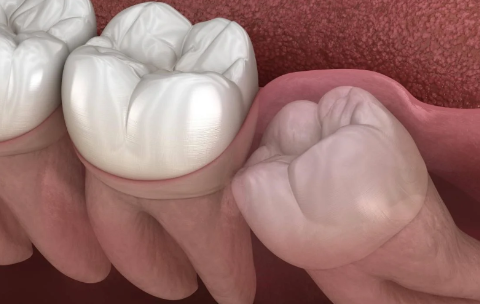

2、影響鄰近牙齒:如果牙齒生長位置不正確而擁擠,就有可能對鄰近牙齒造成損害,使咀嚼功能嚴重受損,因此需要拔除智齒。